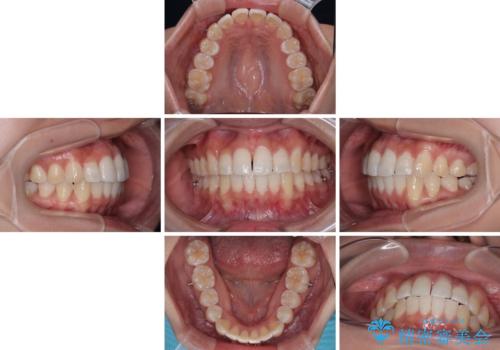

前歯のデコボコを治したい インビザライン矯正

- 上下前歯の叢生を気にして来院された患者様です。

インビザラインでの治療を希望されていて、デコボコの程度が中等度であり、安価なパッケージにて対応可能と判断されたため、インビザライン・モデレートを用いて矯正治療を行うこととしました。